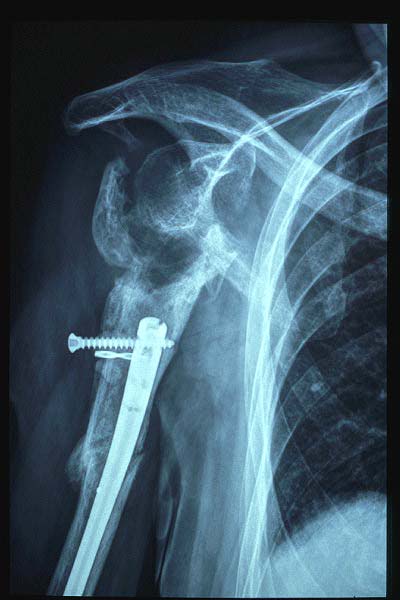

Fractura impactada de húmero .

Fractura compleja de húmero.